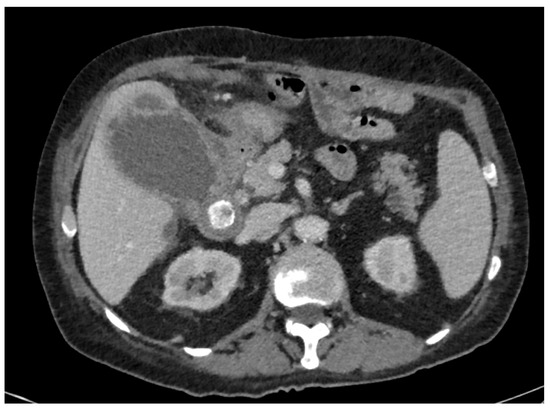

Among the 105 patients included in the study, the main reasons for not performing early LC were: symptom duration greater than 3 days according to internal departmental guidelines (n = 47, 44.76%), severe inflammatory status (n = 23, 21.90%) (Figure 2), and anticoagulant or dual antiplatelet therapy (n = 17, 16.19%). Additional reasons included significant comorbidities (n = 14), patient refusal (n = 3), and one case of suspected colobiliary fistula. Regarding the indications for PTGBD realization, the most common were worsening inflammatory markers despite appropriate antibiotic therapy (n = 50, 47.62%) and severe inflammatory status (C-reactive protein level > 300 mg/dL or sepsis) (n = 37, 35.24%). Less frequent indications included gallbladder perforation (n = 9) and gallbladder hydrops (n = 3). In six cases, the indication for PTGBD realization were not specified (Table 1).

Figure 2.

Initial CT scan in a 73-year-old man, known for ischemic and rhythmic heart disease anticoagulated with Apixaban, with an ASA score = 3, presenting pain for 2 weeks, with a significant inflammatory syndrome (CRP = 251 mg/L).